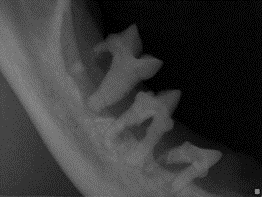

The surgical management is currently considered the standard of care for stomatitis. This involves extraction of teeth as the major plaque-retaining surfaces. The extractions must remove the entire tooth, even retained roots of teeth previously lost. The procedure should only be done in a facility equipped with dental X-rays and by a veterinarian with experience in performing extractions in cats.

There are two methods described for surgical management: caudal (all teeth behind the canines) versus full mouth extractions. Caudal extractions are an option only in cases where the front teeth (incisors) and the fangs (canines) are healthy, with no resorptive lesions or periodontal disease. Dental X-rays are mandatory in making that assessment. It is very common to find tooth resorption and periodontal disease in cats affected by stomatitis.